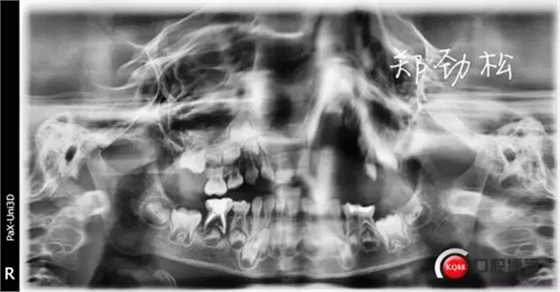

一月后永久充填復查時可見炎癥明顯好轉,近中根超充的糊劑也吸收了,臨床癥狀也消失了。